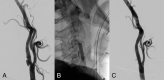

Background and purpose: Mechanical thrombectomy for patients with acute ischemic stroke with tandem occlusions has been shown to present varying reperfusion successes and clinical outcomes. However, the heterogeneity of tandem occlusion etiology has been strongly neglected in previous studies. We retrospectively investigated patients with acute ischemic stroke atherothrombotic tandem occlusion.

Materials and methods: All consecutive patients with acute ischemic stroke with atherothrombotic tandem occlusions treated with mechanical thrombectomy in our center between September 2009 and April 2015 were analyzed. They were compared with patients with acute ischemic stroke with dissection-related tandem occlusion and isolated intracranial occlusion treated during the same period. Comparative univariate and multivariate analyses were conducted, including demographic data, safety, and rates of successful recanalization and good clinical outcome.

Results: Despite comparable baseline severity of neurologic deficits and infarct core extension, patients with atherothrombotic tandem occlusions were older (P < .001), were more frequently smokers (P < .001), and had globally more cardiovascular risk factors (P < .001) than the other 2 groups of patients. The patients with atherothrombotic tandem occlusions had significantly longer procedural times (P < .001), lower recanalization rates (P = .004), and higher global burden of procedural complications (P < .001). In this group, procedural complications (OR = 0.15, P = .02) and the TICI 2b/3 reperfusion scores (OR = 17.76, P = .002) were independently predictive factors of favorable clinical outcome.

Conclusions: Our study suggests that atherothrombotic tandem occlusions represent a peculiar and different nosologic entity compared with dissection-related tandem occlusions. This challenging cause of acute ischemic stroke should be differentiated from other etiologies in patient management in future prospective studies.